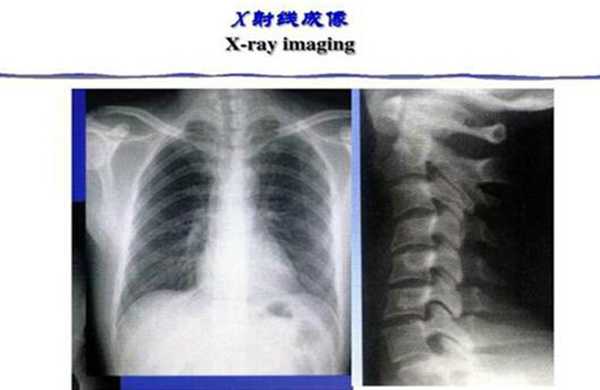

现在的x射线主要被用于医疗诊断、医学治疗以及工业领域。我们所最为熟知的便是x光在医疗方面的应用,这是最为广为所知的查体方式,可以检查人类的身体某一部分,也是最早应用的非创性内脏检查技术。现代世界十大工程奇迹之一钱德拉X射线天文台也是在x射线的基础上被发明出来的。